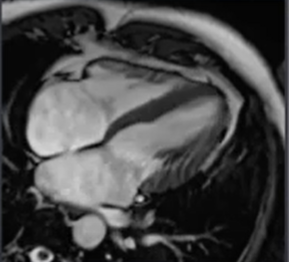

IRM cardiaque